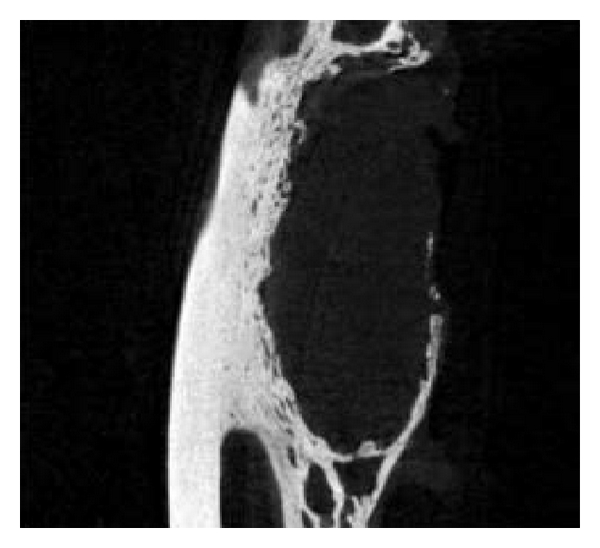

3.4. Micro-CT Examination

Micro-CT examination of 5 rabbits (2 from group A, 2 from group B, and 1 from group C) was conducted 3 months after surgery. The shapes of the rabbit bones at 3 months were shown in Figure 4. The bone defect in group A was not completely repaired, which in group B was completely repaired, while group C showed typical bone nonunion. The number of trabeculae per mm in groups A, B, and C was 0.40, 0.17, and 0.34, respectively. The bone mineral density in groups A, B, and C was 1.25434 mg/cc, 1.32521 mg/cc, and 1.3349 mg/cc, respectively, and the high bone density in group C resulted from osteosclerosis. The mass losses of PLLA and PLLA/PCL were 63.575% and 67.195%, respectively. These two scaffolds have fast initial degradation rate and then slowed down and cannot completely degrade 3 months after implantation.

(a)

(b)

(c)